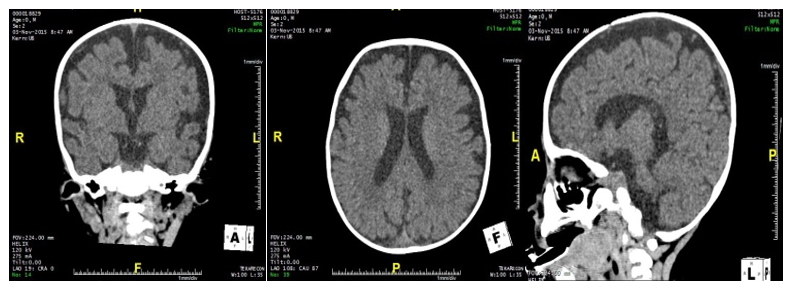

Nervous System Lesion in Infants with Vitamin B12 Deficiency Anemia

Taranushenko Tatiana E, SO Falaleeva, EV Borisova and NYu Makarevskaya